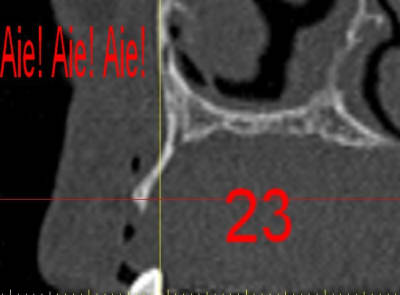

dar23_ts4djh.jpg

La première diapo est un essai pour justifier le concept (os non destiné à une utilisation greffe)

la deuxième est "tapée" dans une tête de femur de mauvais qualité (rejetée)

la troisième et suivante ce sont "les greffons" définitifs.